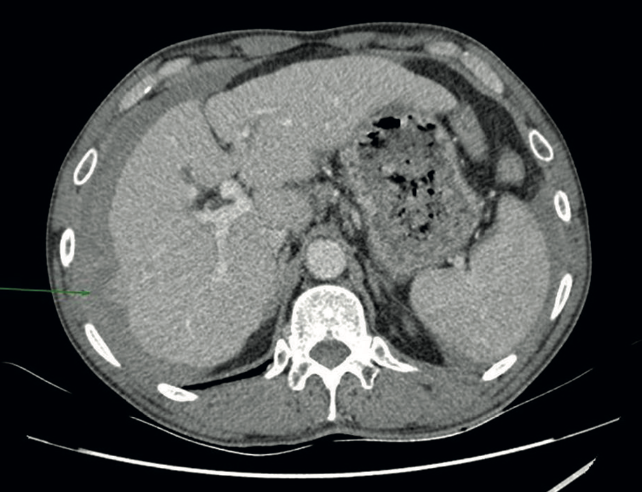

Material y Métodos: Paciente varón de 50 años que debuta con cuadro de hemoperitoneo espontáneo tratado de forma conservadora. Tras completar el estudio es diagnosticado de CHC sobre hígado no cirrótico con sobreinfección viral VHB/VHD catalogado como estadio 0/A de la Barcelona Clinic Liver Cancer (BCLC).

Resultados: Se realiza subsegmentectomía del segmento VI y VII. Presenta postoperatorio tórpido con diagnóstico de carcinomatosis peritoneal y diseminación hepática al mes de la cirugía.

Discusión: El CHC exofítico no dispone de una definición estandarizada. Su manejo quirúrgico y opciones de tratamiento intervencionista pueden precisar de adaptaciones específicas del algoritmo BCLC. Las lesiones exofíticas presentan un riesgo aumentado de rotura espontánea. Es necesario profundizar en su estudio para aportar un abordaje multidisciplinar efectivo.